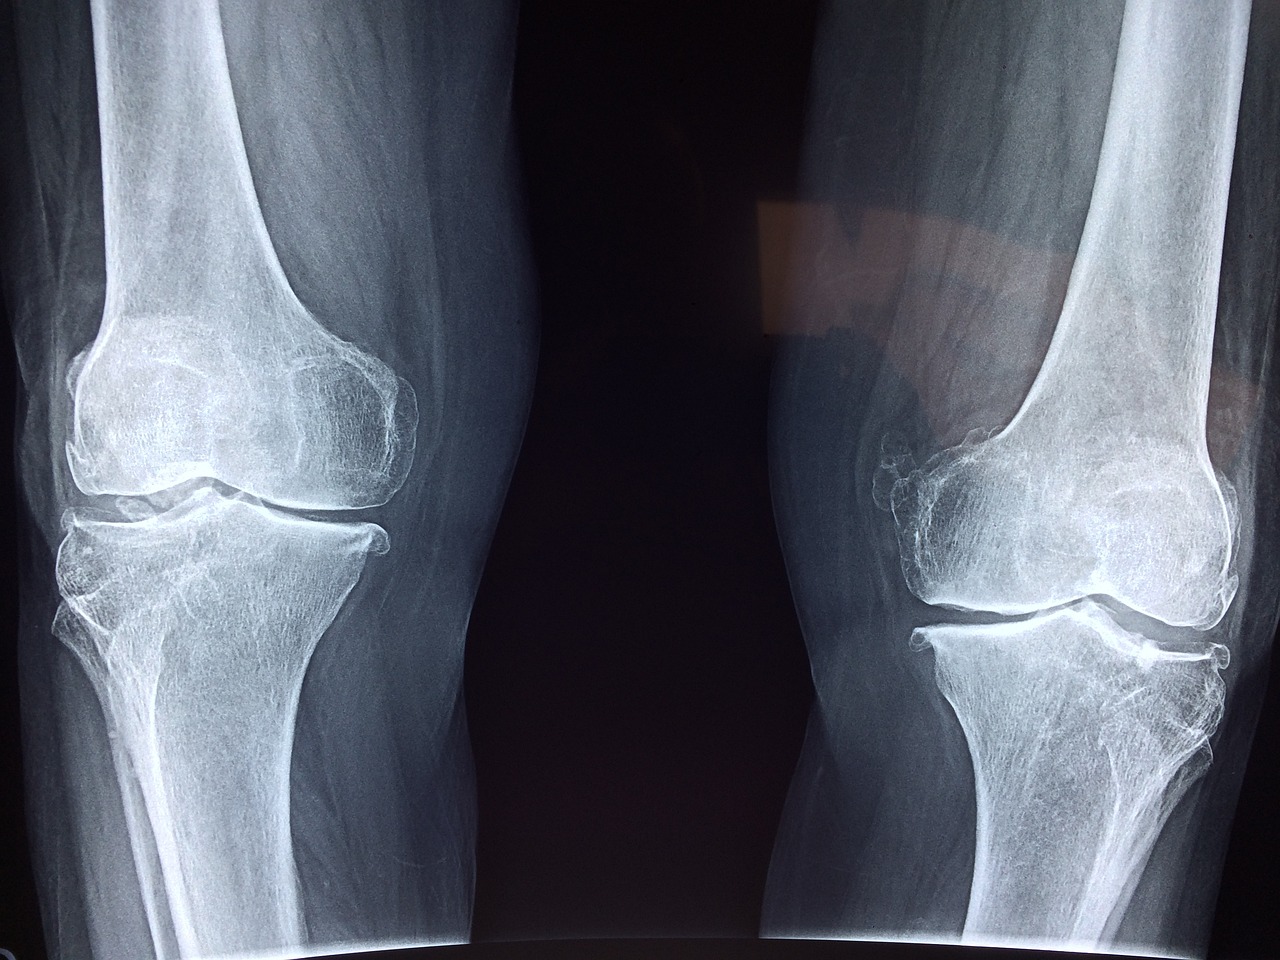

- 관절 부종: 통풍 발작 시 관절 주위에 염증이 발생하여 부종이 발생할 수 있습니다. 부종은 통풍이 있는 관절 주변의 피부가 붉게 변할 수도 있습니다.

- 강직성: 관절 통증과 염증으로 인해 환자는 해당 관절을 움직이는 것이 어려울 수 있습니다. 강직성은 통풍 발작이 지속되는 동안 지속될 수 있습니다.

통풍 발작은 대부분 한 관절에만 영향을 주지만, 경우에 따라 여러 관절에 영향을 줄 수도 있습니다. 통풍은 보통 급성 발작을 일으키고, 발작이 종료되면 증상이 완전히 사라질 수 있습니다. 그러나 통풍이 반복되거나 관리되지 않으면 관절 손상이 발생할 수 있으므로, 증상이 발생하면 의료 전문가와 상담하는 것이 중요합니다.